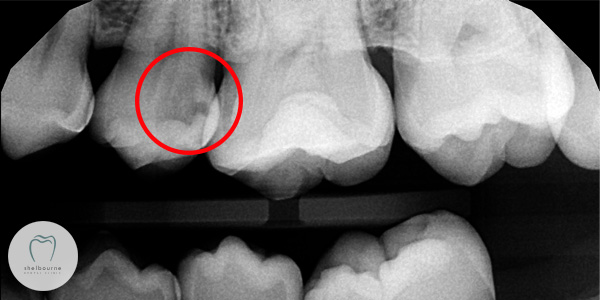

See that dark area which I’ve circled in red? Know what it is? Yep…. it’s DECAY! Dental Decay. We dentists call it “dental caries”. And lots of it there too. This decay is well into the tooth, to the point where it is practically sitting on top of the nerve (the black line going up the root of the tooth).

How has this happened? The top of the tooth looked absolutely fine? You see, the problem here is not on the top of the tooth. It’s BETWEEN the teeth. Food gets stuck between the teeth and if interdental cleaning (flossing and interdental brushing) isn’t performed, decay sets in between the teeth.